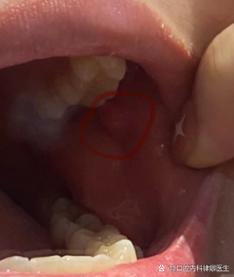

口腔上颚硬包是啥?要紧吗?

(图片来源网络,侵删)